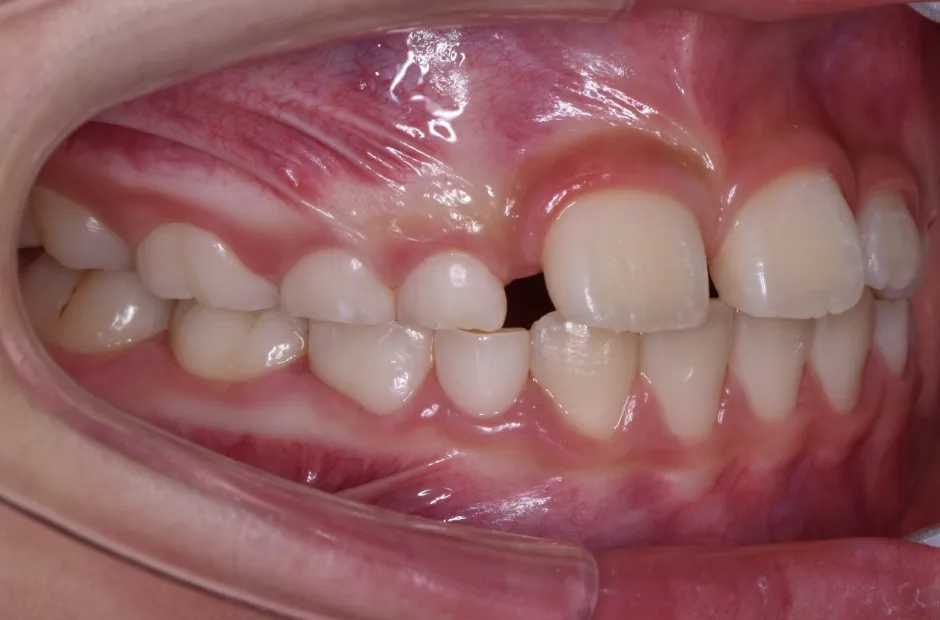

治療症例

ブラケット矯正

前歯部反対咬合

| 診断名・主訴 | 前歯部反対咬合 |

|---|---|

| 年齢・性別 | 14歳・男性 |

| 治療期間・回数 | 1年2か月 |

| 治療に用いた主な装置 | ブラケット矯正 |

| 抜歯部位 | なし |

| 治療費 | 60万円(税抜) |

| リスク・副作用 | 装置による違和感・疼痛・歯肉退縮・歯根吸収・虫歯のリスクなど |

治療前

治療後